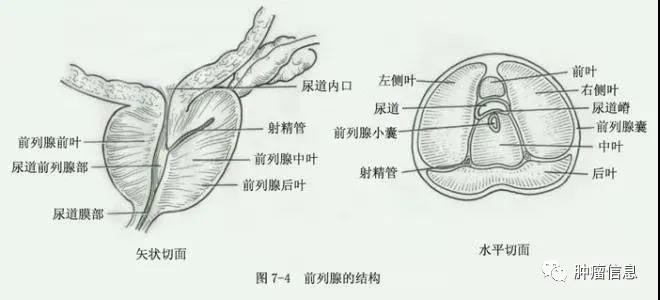

01 前列腺解剖02 前列腺解剖分区 前列腺分为外周带(PZ)、中央带(CZ)、移性带(TZ)、前纤维肌肉基质带(AFMS)。外周带体积最大,占前列腺的70%,在...